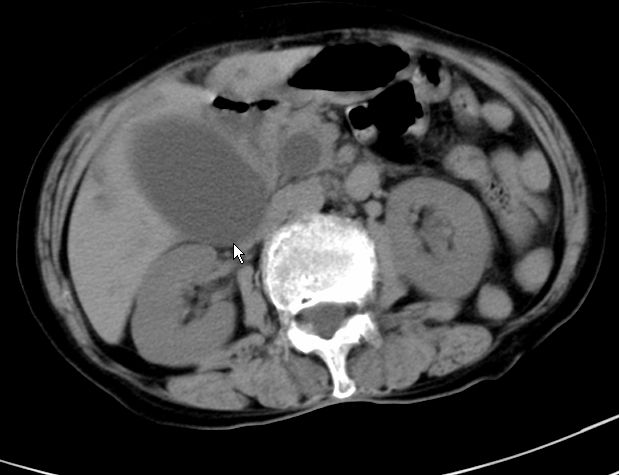

以下是引用zjzjr在2008-12-16 12:49:00的发言:[br]肝内外胆管全程扩张,胆囊明显增大,未见占位征像.建议mrcp.

以下是引用jiangjing在2008-12-16 13:19:00的发言:[br]肝内外胆管全程扩张,胆囊明显增大,扩张胆总管下段径较中上段小,未见胰管扩张,提示胆总管远端梗阻伴感染.建议增强及mrcp 检查

以下是引用朱亮在2008-12-16 12:54:00的发言:[br]胆总管远端应薄层扫描 胆总管逐渐变细 考虑胆系慢性炎症